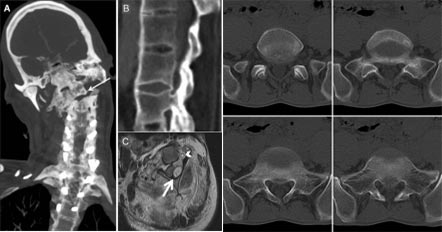

(图:X光片显示,患者治疗前颈椎关节变形、骶髂关节骨质受损)

X线片显示:患者骶髂关节的中下部两侧,可见斑点状及块状阴影,边缘呈锯齿状,软骨下有骨硬化,骨质增生。